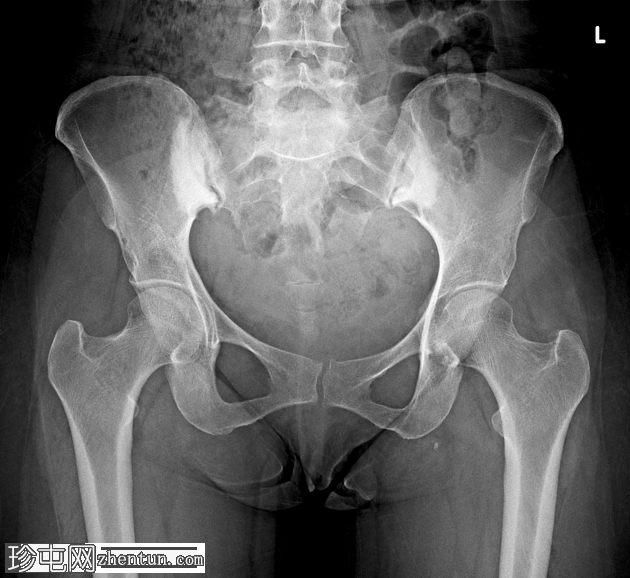

髂骨致密性骨炎

主诉慢性腰痛。无既往外伤史。

年龄:45岁

性别:女

X光片

双侧髂骨和骶骨呈三角形硬化(右 > 左),骶髂关节间隙保留,无糜烂。

本病例的密切鉴别诊断是骶髂关节炎,两种疾病的腰痛病史相似,但骶髂关节炎是一种炎症性疾病,伴有关节间隙缩小和糜烂。